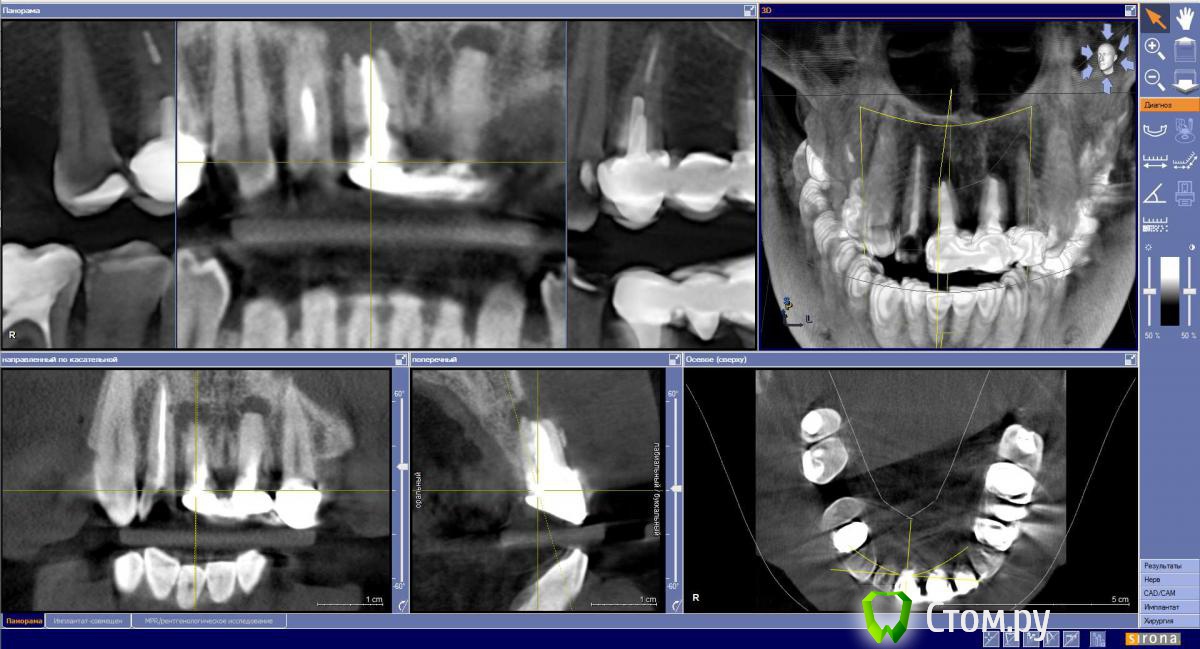

Мне 39 лет 1.1 и 2.1 травма 28 лет назад, повторные кисты после резекции 16 лет назад. Надо удалять, ждать пока нарастет костная ткань и ставит имплантанты. Сколько ждать после удаления для имплантации? Смущает срок 6 мес межу удалением и установкой имплантантов. Действительно так долго?

1.2 надо перелечивать канал или нет?

2.2. депульпировать, надо снимать коронки или можно через коронку?

достаточно подождать около 2х мес. Скорее всего костная пластика понадобится.

сейчас заканчиваю такого же пациента. удаление обоих с цистэкомией и подсадкой кости(искусственной), через 6 месяцев импланты, через 4 месяца формирователи и коронки